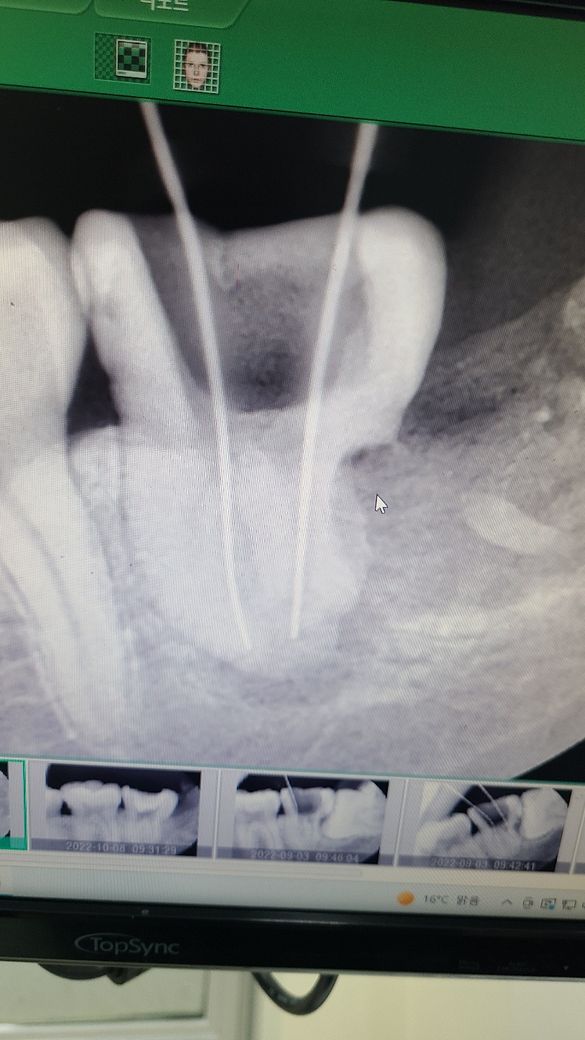

사랑니로 인하여 이미 앞쪽 어금니의 뿌리가 염증에 의해 녹은 상태입니다. 신경치료를 하더라도 예후가 매우 안 좋아 보이며 해당 부위의 어금니가 신경치료 도중 뿌리도 일부 부러진 상태입니다. 살려서 쓸 수 없을 정도로 훼손된 상태이며 더 이상 신경치료를 진행하기보다는 발치 이후 임플란트 등을 하셔야 합니다.